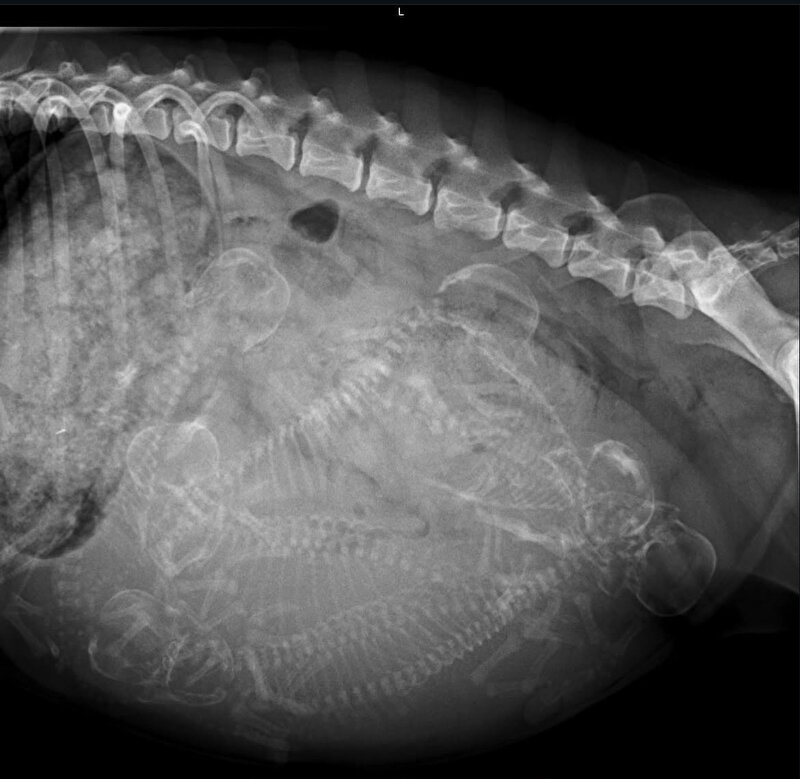

Het kan ook wel. Maar de ervaring is dat je dan gewoon een slecht beeld hebt. Als je wacht tot 55+ dagen zie je het veel duidelijker. En daar doe je t voor..

En altijd van 2 zijkanten foto’s maken. Soms liggen pups wat verstopt en dan zie je ze vanaf de ene kant niet liggen.

En de reden dat ik daar over “zeur” is dat de baarmoeder een vorm van een Y heeft. Dat wil zeggen: 1 baarmoederhoorn linkerzijde hond en 1 rechterzijde. Op de eerste foto lijkt een 5e aanwezig, die op de 2e foto bijna niet meer te zien is. Wat kan betekenen dat er nog steeds een nr 5(of6) aanwezig is, want wat je ook op de foto ziet is een gevulde darm. Ter hoogte van de 3 schedels is het dus te vol van ontlasting om een goed beeld te krijgen.

Maar vooraan vind ik het beeld ook te vaag om duidelijk te zien wat daar zit. Ik zou dus zeker nieuwe foto’s maken en dan van beide kanten.

Het zijn in ieder geval minimaal 4 pups, maar het zou me niets verbazen als er straks nog meer uitkomen.

floorsil schreef:Volg gewoon even mee.maar als ik hoofdjes of ruggengraten tel ik er 6 . Hoe zit dat? Heel veel succes met de laatste loodjes.